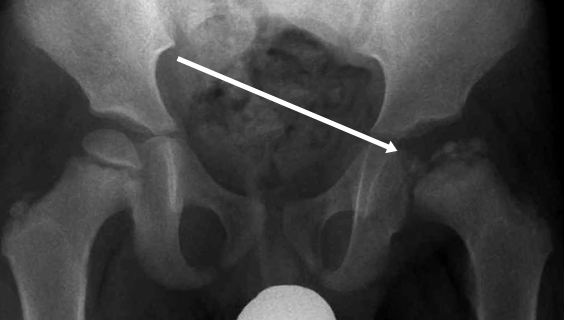

Епифизиолиза на бедрената глава (SCFE)

Епифизиолиза на бедрената глава е състояние, засягащо тазобедрената става. Епифизиолизата на бедрената глава е сериозно ортопедично състояние при деца и юноши, най-често се среща при 10-16 г. възраст. При това състояние главата на бедрената кост се измества спрямо шийката през растежната пластинка.

Получава се,когато разстежната пластинка на костта е отслабена, което кара горната част на бедрената кост да се изплъзне от нормалното си положение. Среща се през периоди на бърз растеж- началото на пубертета. По-често се среща при момчета. Симптомите включват: